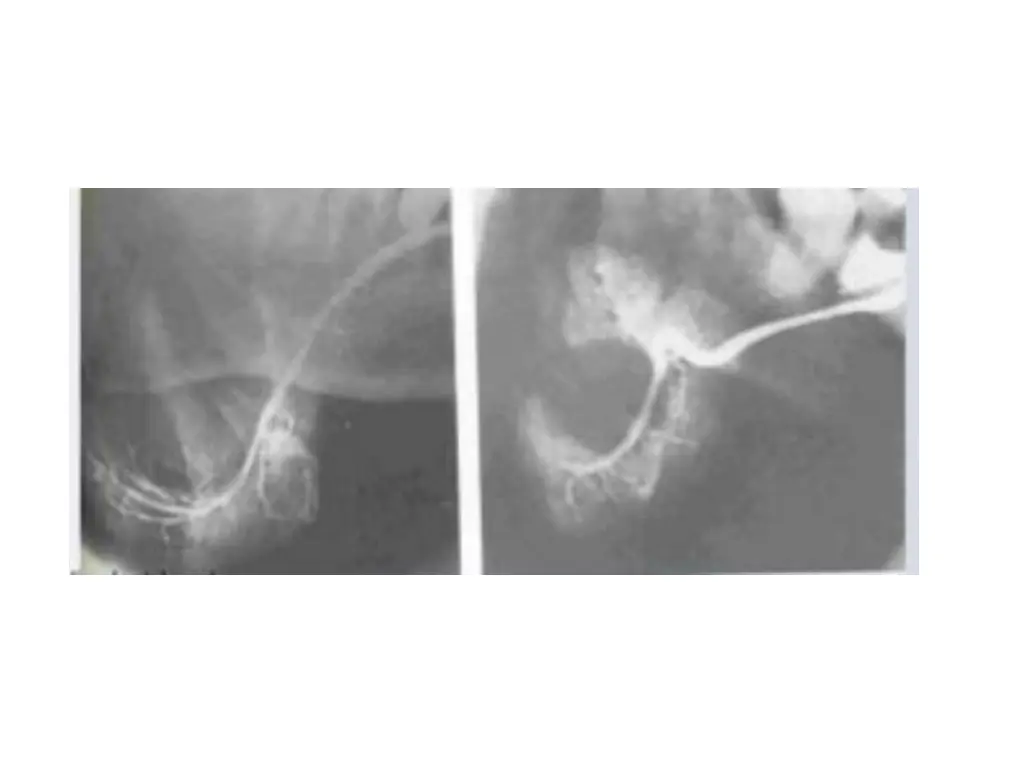

Benign tumors Typically have well defined margins and are most apparent on CT and MRI Coz of higher density of submandibular gland, which can equal that of neoplasm and obscure the tumor Iv contrast enhancement is required during CT examination This causes the tumor to appear more r opaque coz the vascularity of tumor is greater than adjacent salivary gland tissue

US benign masses are typically sharply defined, less echogenic than parenchyma, and of essentially homogenous echo strength and density Benign tumors appear as low intensity (dark) or high intensity (light) signals on MRI Relative intensity of signal may indicate presence of lipid, vascular or fibrous tissues Space occupying lesions ducts are compressed or smoothly displaced around the lesion (ball in hand appearance)

Benign mixed tumor Syn: pleomorphic adenoma CT sharply circumscribed, infrequently lobulated and essentially round homogenous lesion with higher density than adjacent gland Calcifications within tumor are well depicted on CT Various tissue signals on MRI: Relatively low / dark in T1 weighted images Intermediate on proton density weighted images Homogenous high density / bright on T2 weighted images

Foci of low signal intensity / dark areas usually represent areas of fibrosis or dystrophic calcifications If a calcification is present (signal void), diagnosis favors a benign mixed tumor Tumor appears cold spot on scintigraphy Solid tumors larger than 5mm are usually well visualized